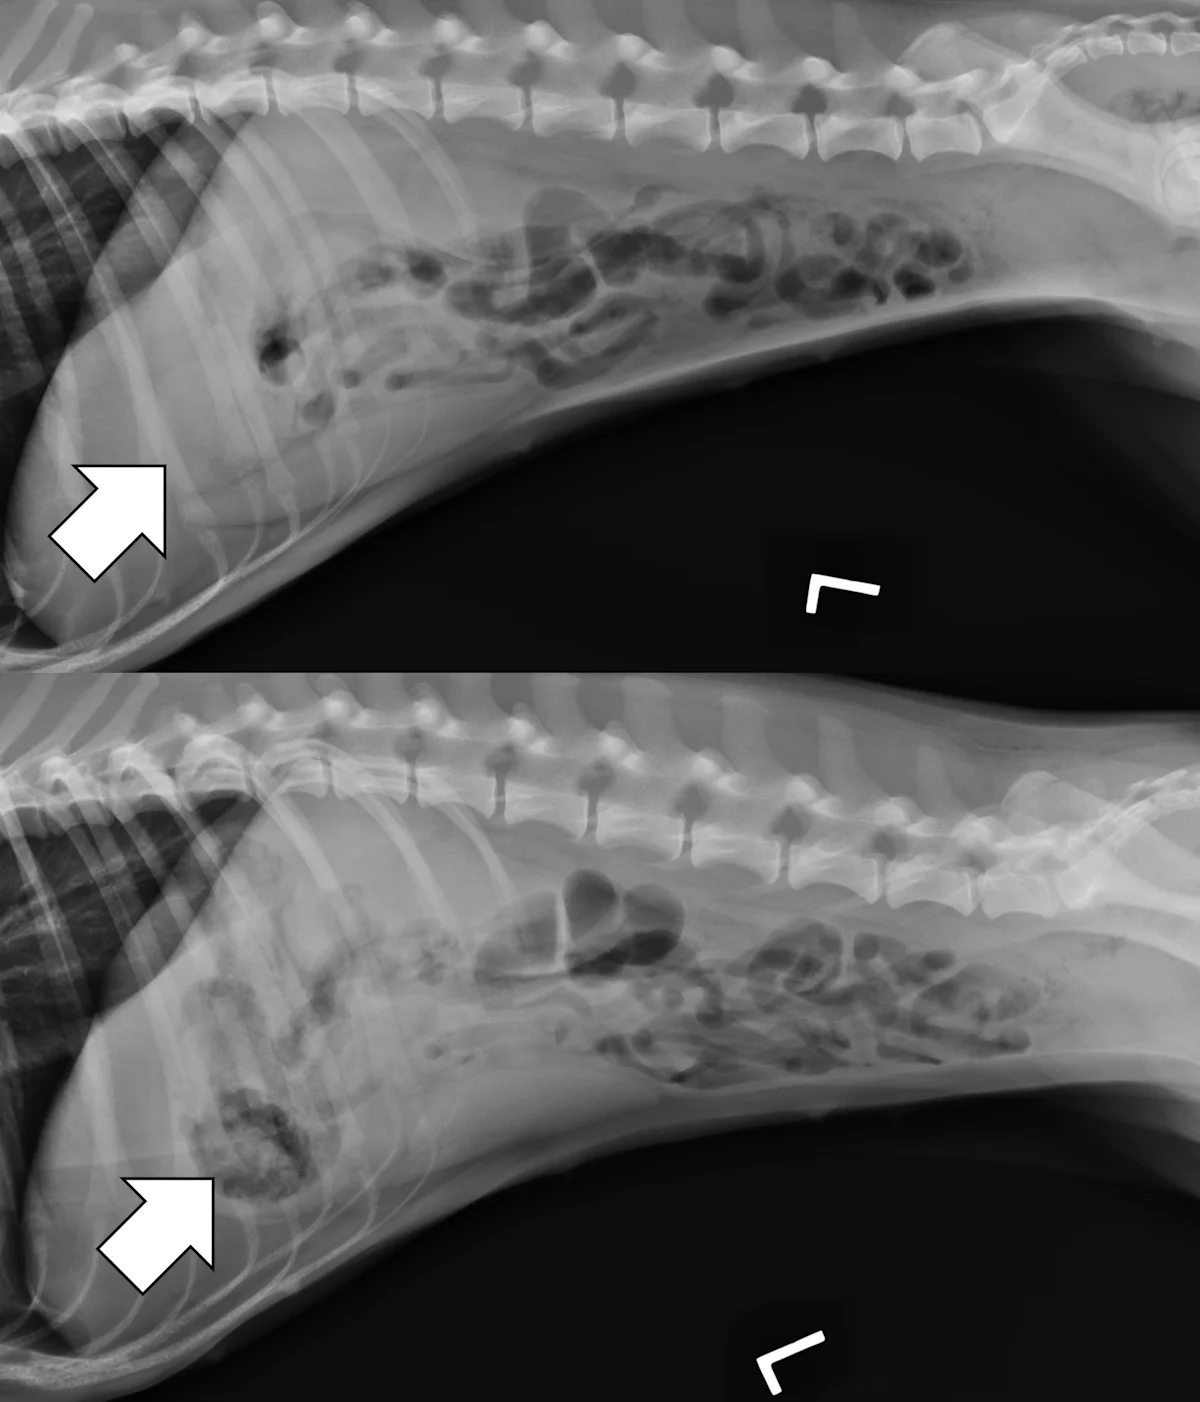

Evaluate the peritoneal space for decreased serosal detail and/or free gas, the combination of which strongly suggests septic peritonitis secondary to GI perforation (Figure 2).

Right lateral and ventrodorsal abdominal radiographs of a 10-month-old neutered male pit bull with a small intestinal mechanical obstruction of undetermined etiology. The stomach is moderately dilated with fluid and gas (pound signs), and there is moderate segmental dilation of the small bowel with stacking and hairpin turns (asterisks). Peritoneal serosal detail is diffusely decreased with a small, tear-drop–shaped intraperitoneal gas bubble between the liver and stomach (arrow) consistent with septic peritonitis secondary to presumed GI perforation.